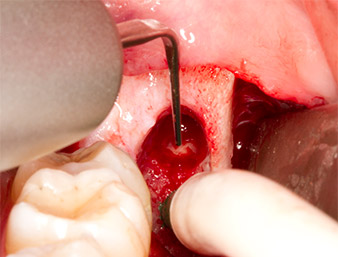

The same activated instrument was inserted into the root canal and loosened the fragment as a result of its micro-oscillating vibrations (Fig. 9, 10).

It was then possible to remove the approximately six-millimetre-long root remnant in one piece with the P1 attachment (Fig. 11).